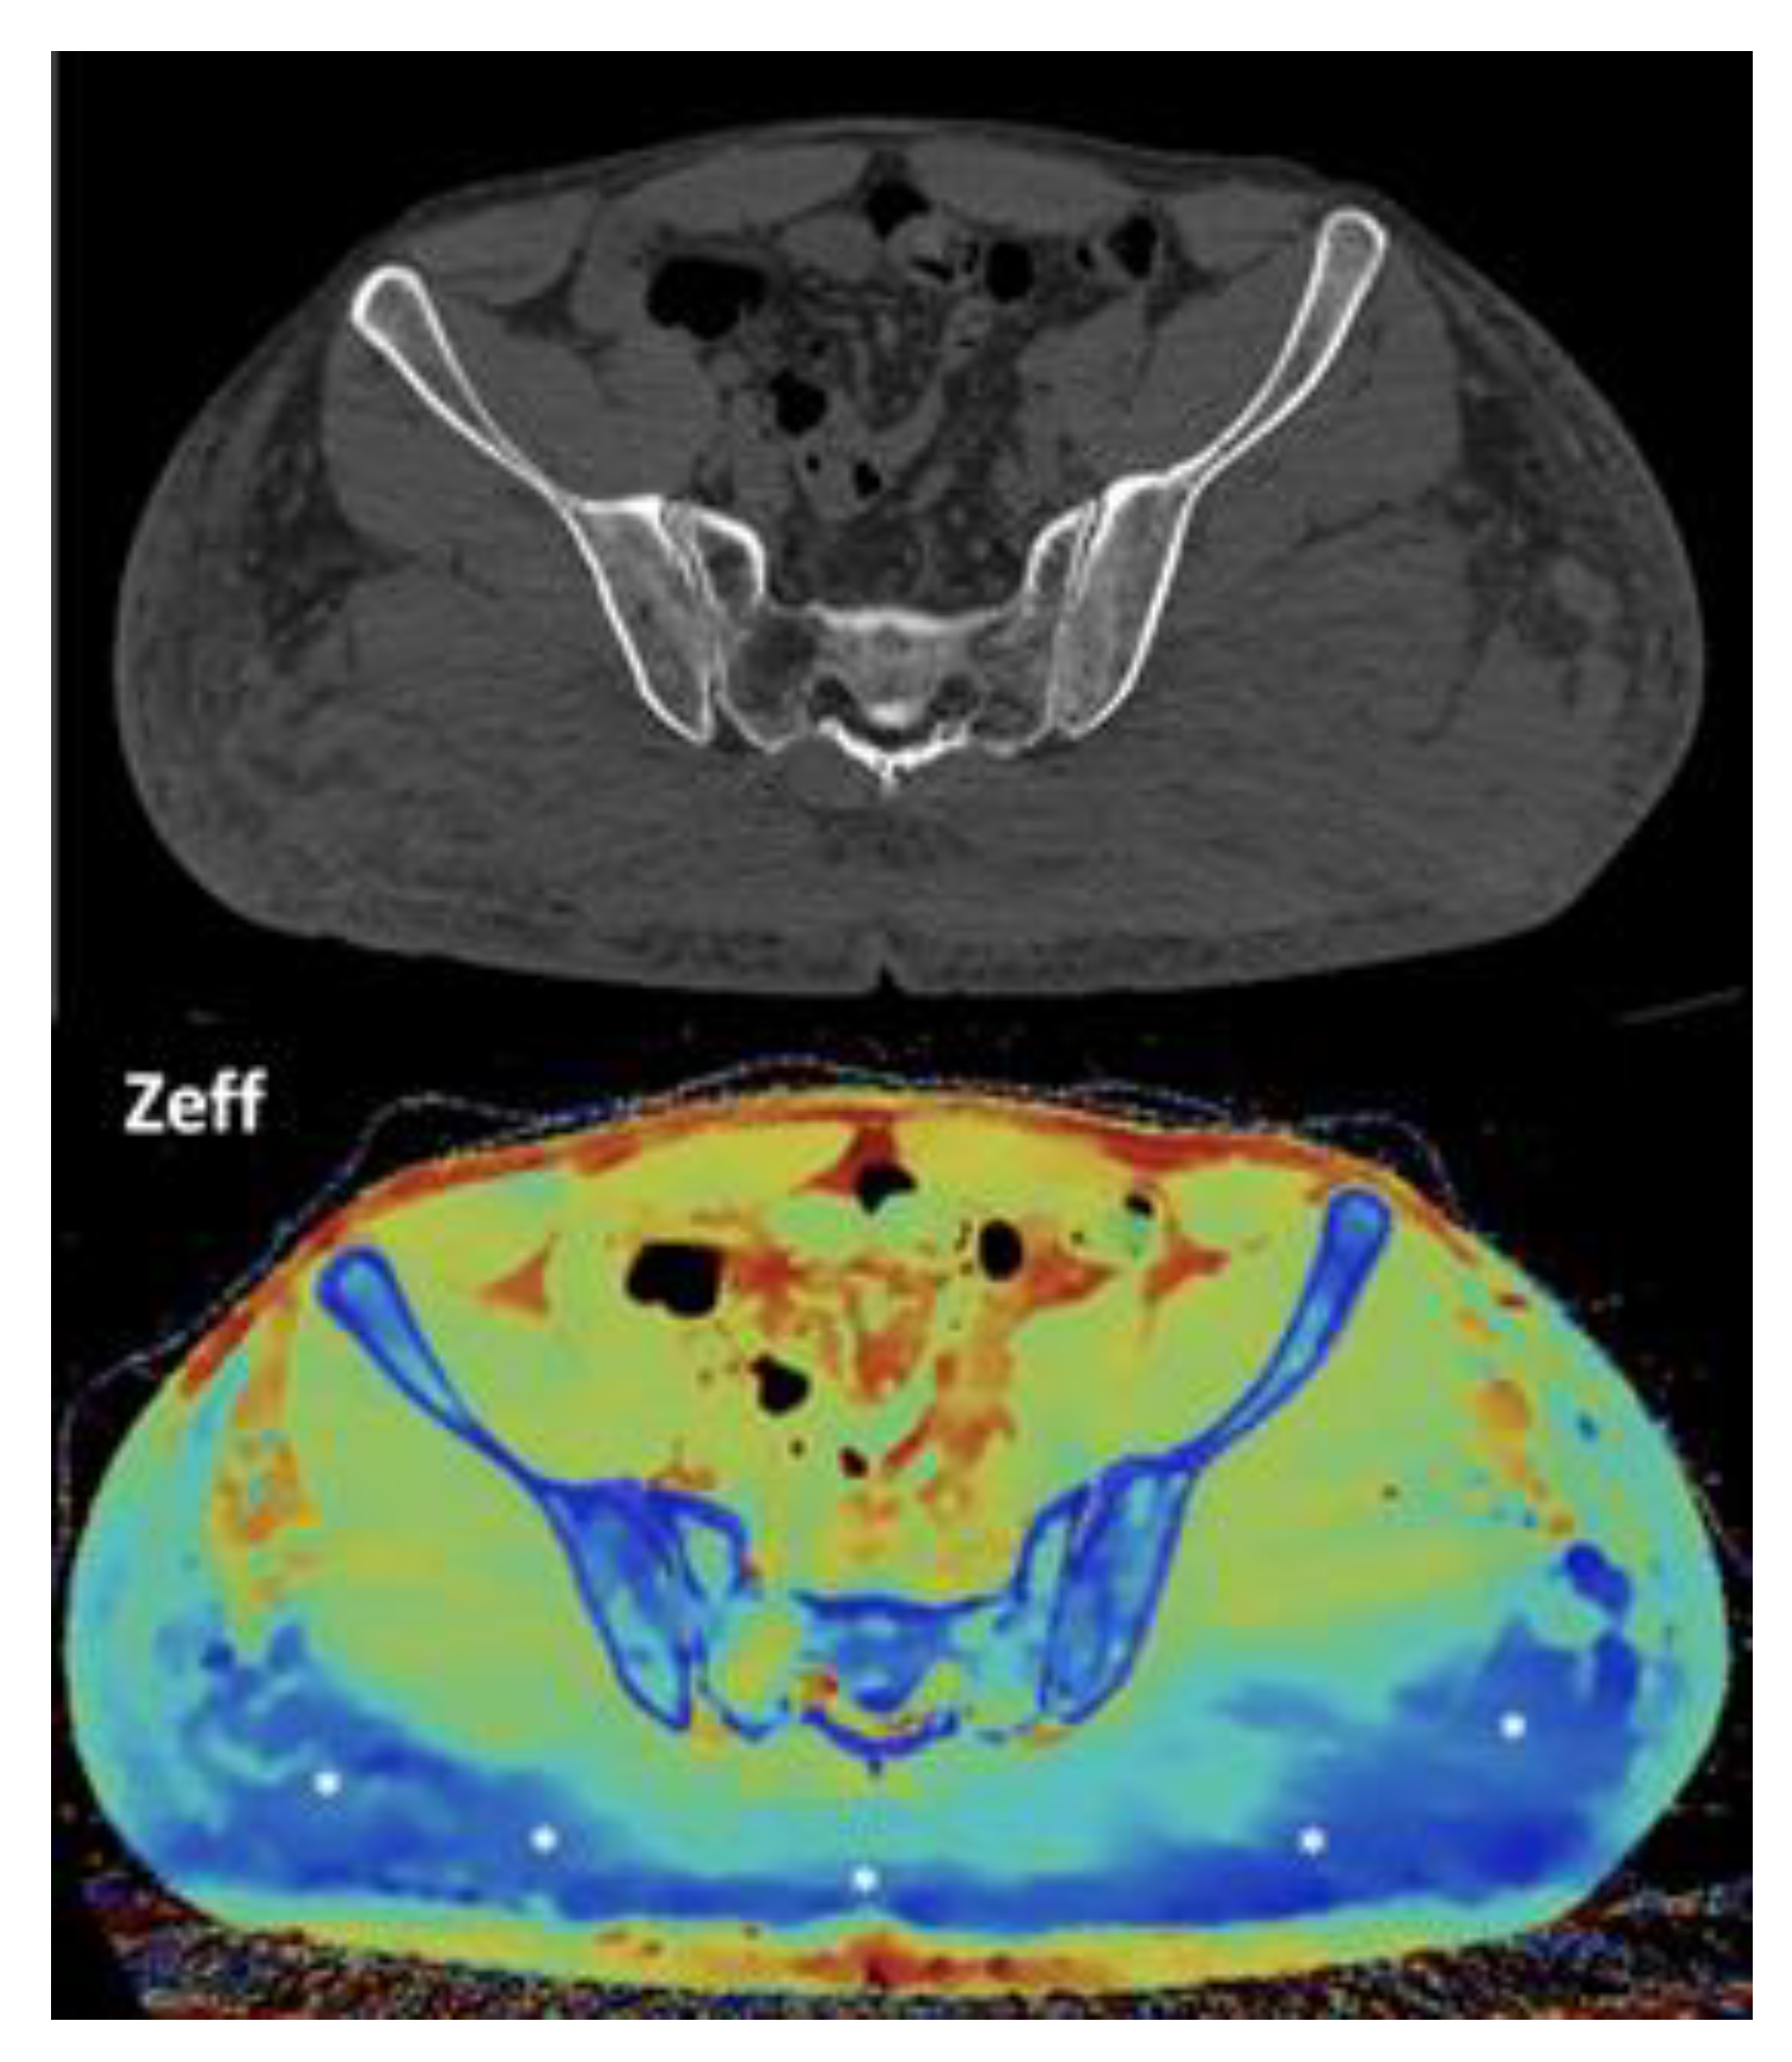

- Imaging of body composition is another growing application of DECT imaging that can be used to improve the evaluation of muscle tissue, visceral adipose tissue (VAT), and subcutaneous adipose tissue (SAT) compartments. SAT and VAT assessment is of special interest in diseases related to metabolic syndrome and critically ill patients [46]. Moreover, sarcopenia is associated with a poorer prognosis in cancer patients [47]. Measuring fat fraction of the skeletal muscle by DECT is a new approach for the determination of muscle quality, an important parameter for the diagnostic confirmation of sarcopenia [48]. In the case of bone mineral density analysis, DECT can provide a more detailed analysis when compared with dual x-ray absorptiometry [49] [Figure 15]. Finally, DECT can also be a useful tool for evaluating silicone implants [Figure 16]. Silicone contains the heavier element silicon (Z value=14), whereas soft tissue predominantly comprises lighter elements, depicting the presence of silicone within the soft tissues in cases of silicone gel breast implant rupture and LNs silicone spread [50].